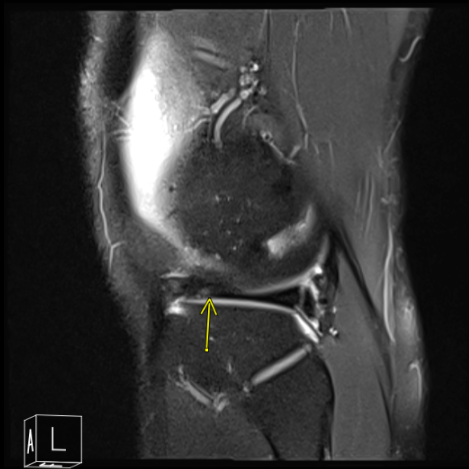

We agreed to go with 3 Tesla MRI of Left knee to final the diagnosis. We also discussed treatment options including Physical Therapy, Injection and also Surgery. Patient will continue to do the Ice/Heat Therapy for it helps a little on his knee condition.

After a week MRI results received and discussed to the patient- showed that aside from joint effusion, there are some degenerative changes seen in the patellofemoral compartment and posterior aspect of the medial tibial plateau which could be related to focal PVNS.

MRI of Left knee